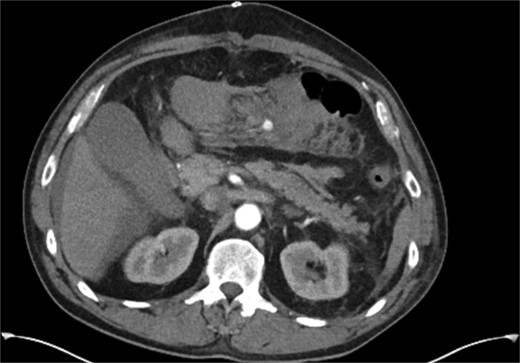

The two-week interval CTA showed that the pseudoaneurysm had increased in size to 2.1 × 1.8 × 1.8 cm (AP × TR × CC) (see Fig. 2). Whilst acknowledging the high risk of gut ischemia, the MDT agreed that intervention was necessary to avoid the risk of rupture. Eight weeks after initial pseudoaneurysm diagnosis, he underwent successful embolization of the MAoD. The embolization procedure was challenging due to tortuosity of the vessel and at the time, deemed too tortuous to stent on table, therefore embolization performed with microcoils (see Fig. 3). He remained clinically asymptomatic with a soft abdomen and had an overnight stay with the general surgery team on standby. His lactate remained insignificant overnight. He opened his bowels and managed a normal diet and was therefore discharged home the following day.

Interval CT angiogram demonstrating enlargement of the false aneurysm (2.1 × 1.8 × 1.8 cm).